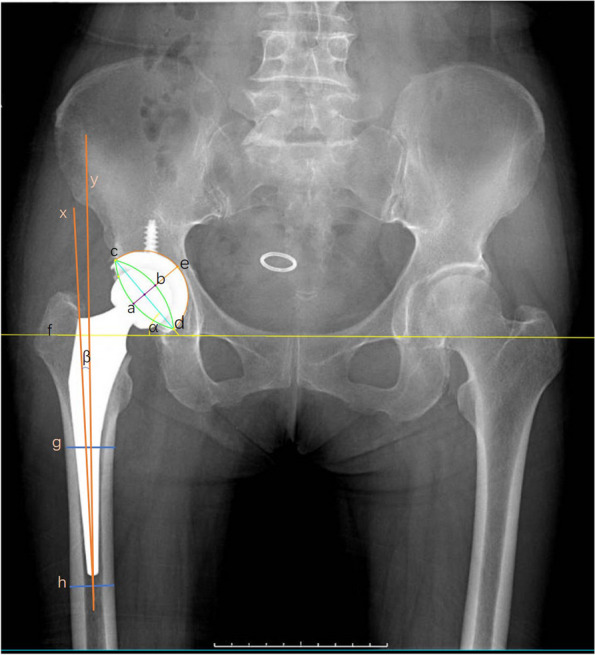

Methods: Collected were data from 350 patients who underwent direct anterior hip arthroplasty between 2008 and 2013, including demographic information, imaging data, Harris hip scores, and surgical complications. Variables, measured radiographically or by CT, included hip offset, leg length discrepancy, component position, and stability within one week after surgery and at the last follow-up. The data were subjected to statistical analysis by using paired t-tests and Pearson chi-square tests.

Results: Data were harvested by follow-up and self-reported questionnaires. The postoperative follow-up lasted for 13.1 years on average (minimum, 10 years; maximum, 15 years), and the overall survival rate of hip prostheses was 96.3%. The mean Harris score at the final follow-up was 91.8 points. After excluding patients with significant preoperative hip deformities, the incidence of postoperative limb inequality (> 5 mm) was 4.9% at the last follow-up, and the incidence of hip offset discrepancy (> 5 mm) was 14.6%. The overall proportion of the acetabular components located in the Lewinnek safe zone was 77.7%, whereas the proportion of femoral prostheses in the safe zone (< 3° inclination) was 94.0%. Based on the revised data and the last follow-up imaging, the total proportion of acetabular and femoral prostheses with a radiolucence of > 2 mm was 5.1%.